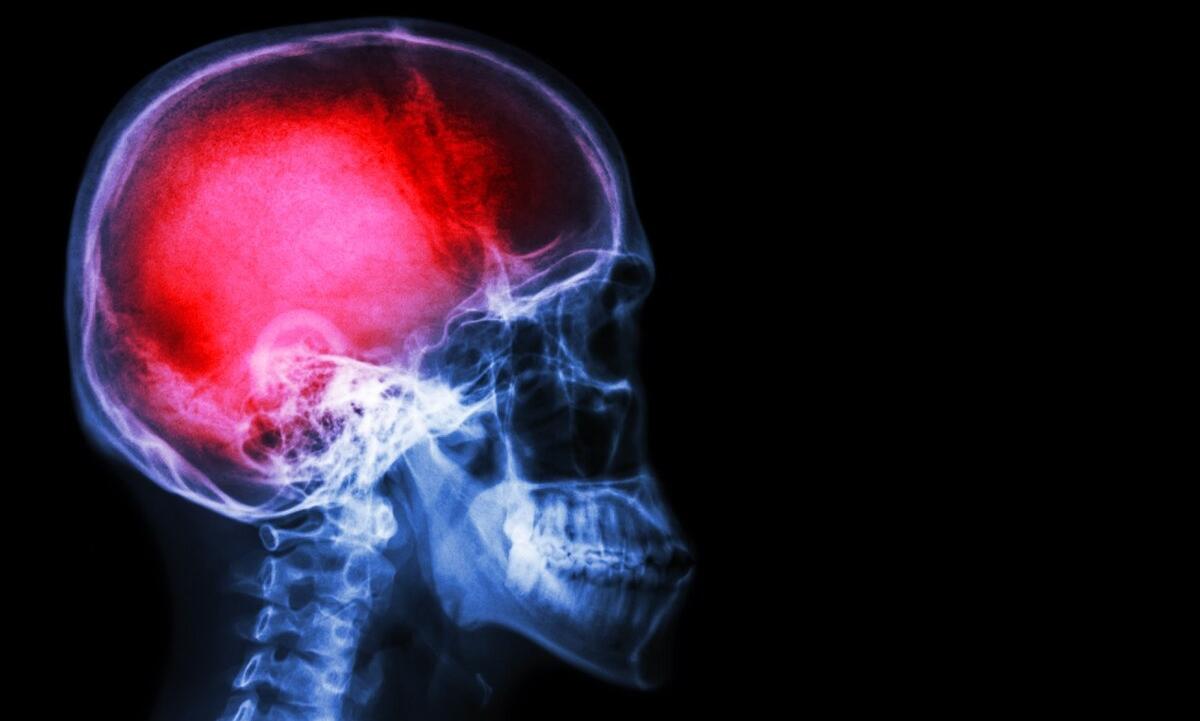

text_fieldsResearch shows that soldiers exposed to shockwaves from military explosives are more likely to develop Alzheimer's disease even if they didn't receive a traumatic brain injury from the blast. The research was published in Brain Pathology, the medical journal of the International Society of Neuropathology.

The study suggested that the blast-induced neurological complications may be rooted in distinct alterations to the tiny connections between neurons in the hippocampus, which is the part of the brain particularly involved in memory encoding and social behaviour.

According to the researchers, the experiment proved an increased risk of Alzheimer's in the people who were exposed to blasts because the changes observed in the experiment were Alzheimer's-type effects in the brain without the recognizable brain damage that is present with TBI (traumatic brain injury).